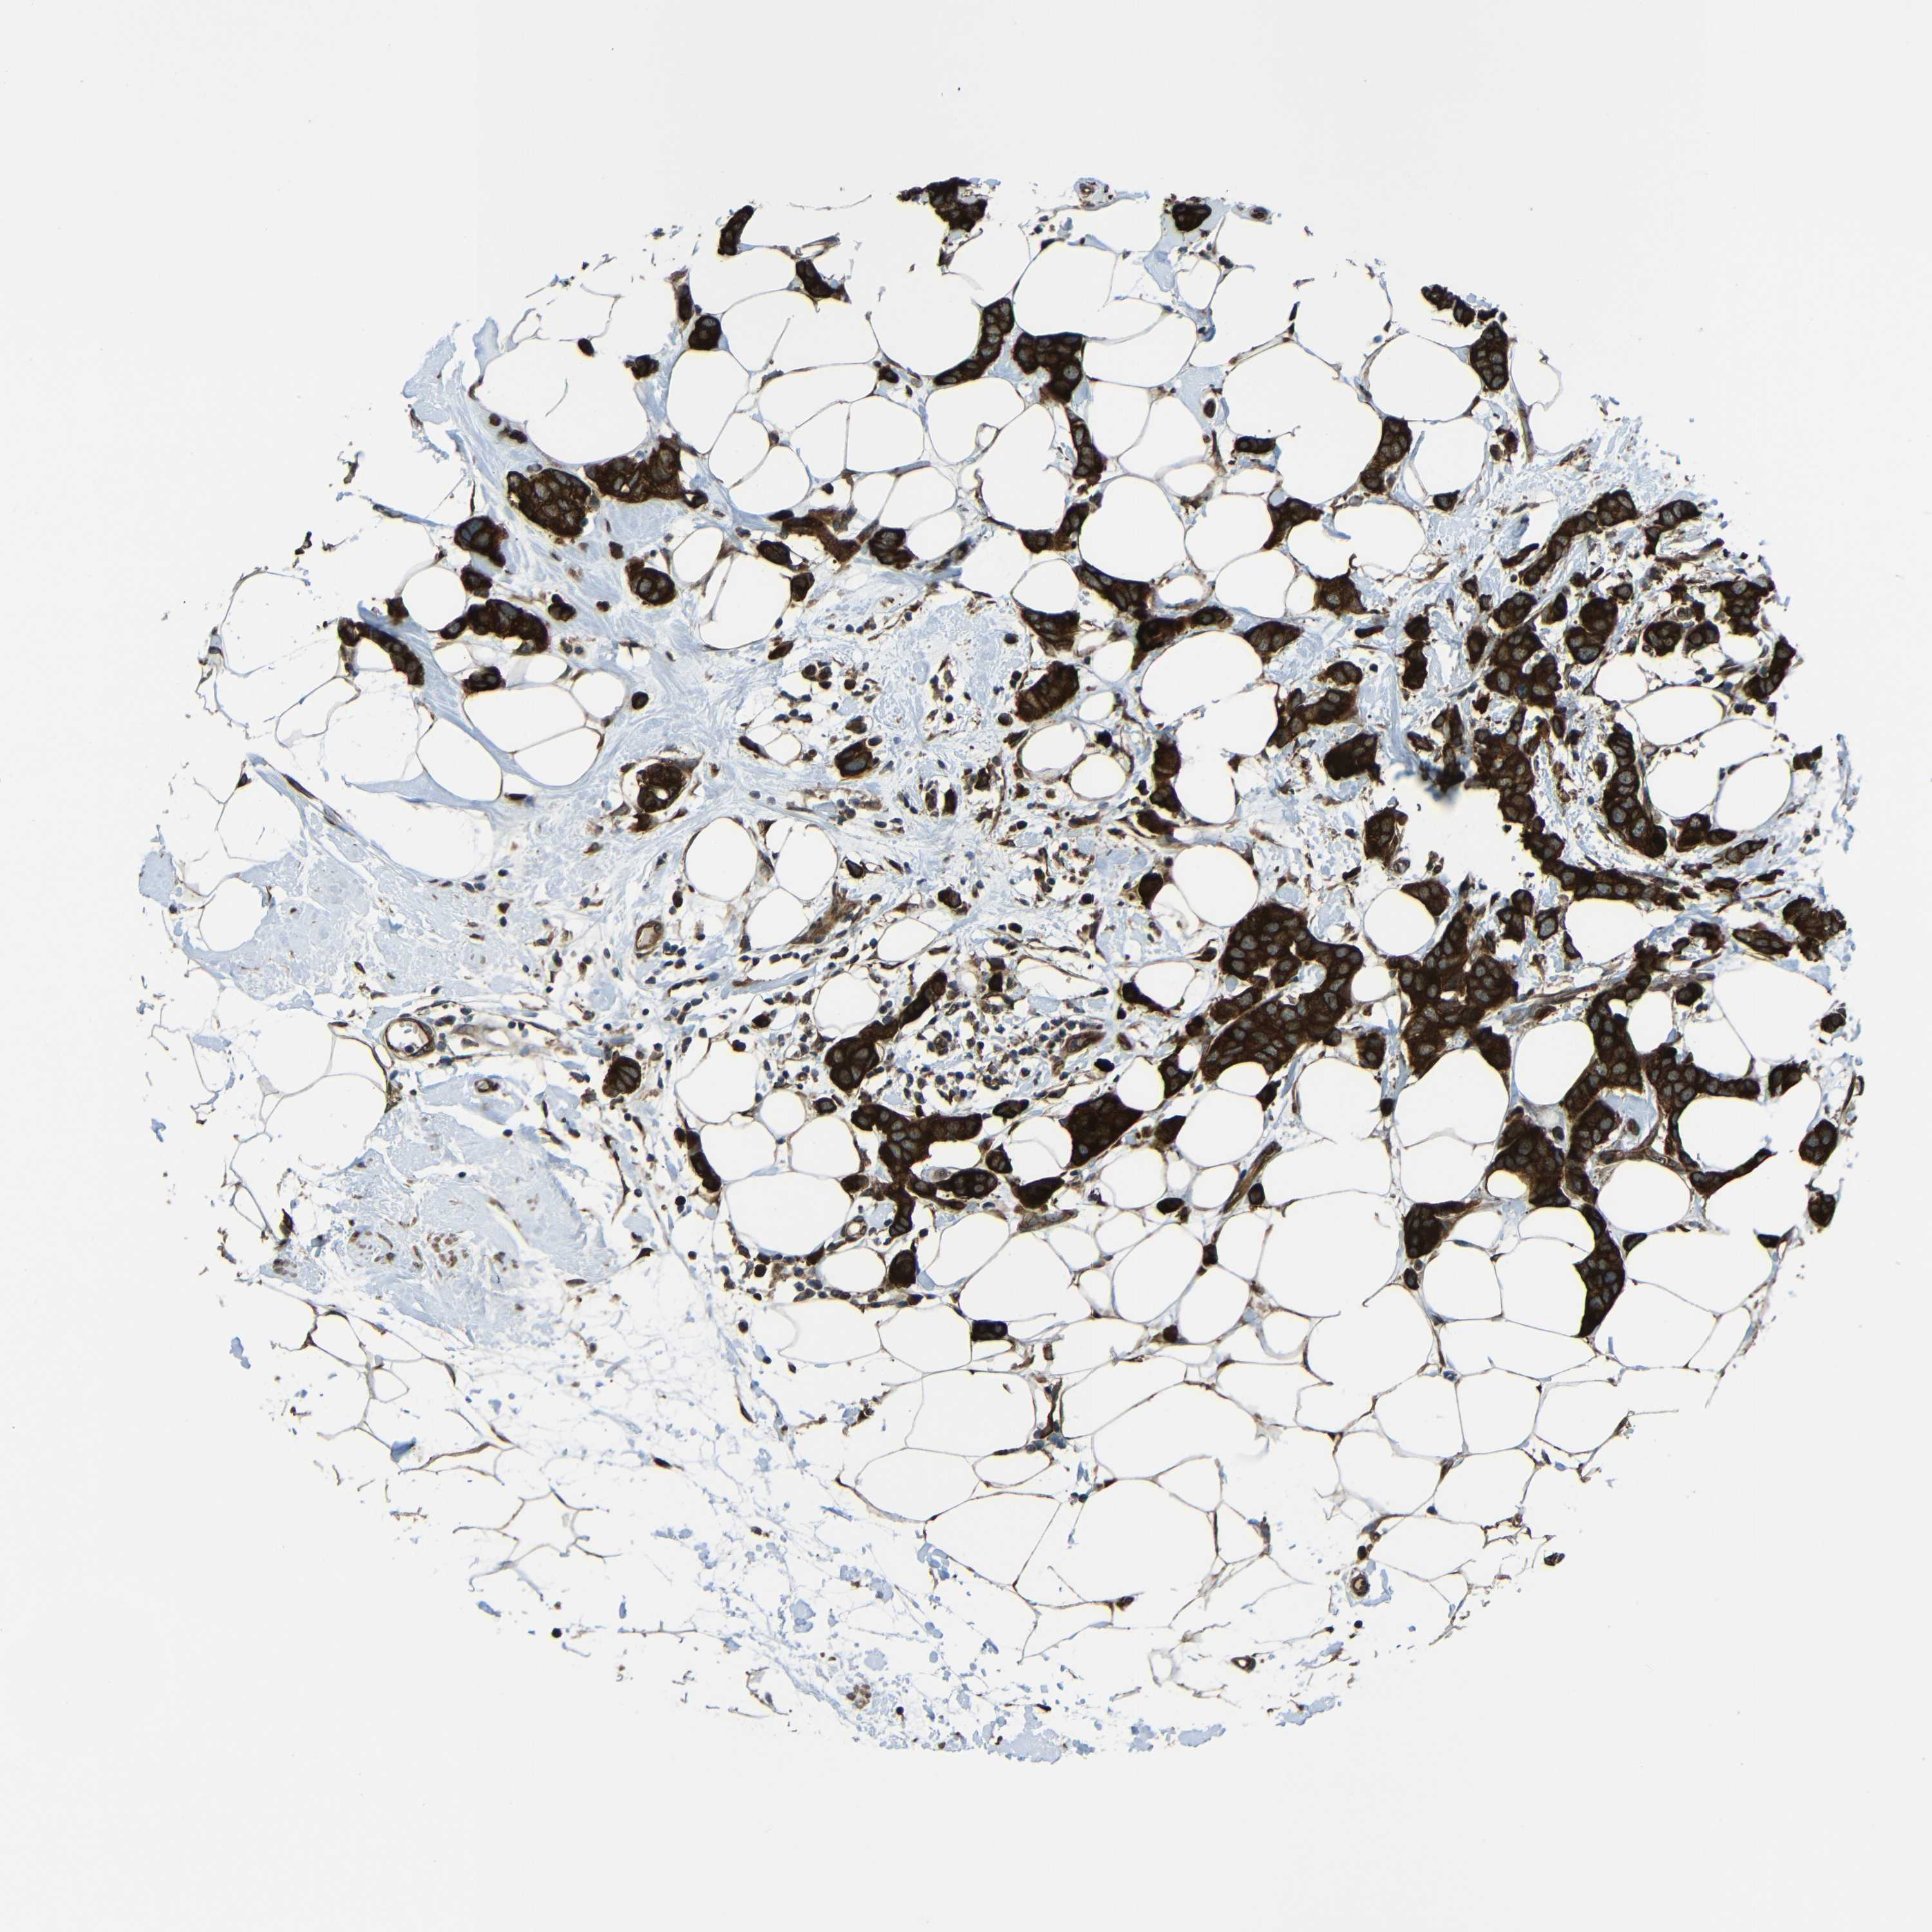

CANCER BREAST CANCER Show tissue menu

BRCA TCGA BRCA VALIDATION PROTEIN EXPRESSION